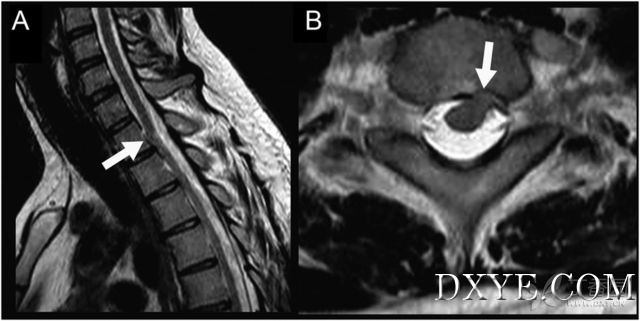

图示脊髓移位,左侧脊髓疝出。

患者,男,42岁,5年前曾有偶发轻部背部创伤病史,近2年出现进行性右腿无力。临床检查显示左侧T2椎体水平以下痛觉、温度觉及轻触觉减退,本体感觉正常,右腿跟腱反射降低,无膀胱功能障碍。脊髓MRI显示T1水平腹侧脊髓疝。从而诊断为脊髓疝。脊髓疝是引起进行性脊髓病的罕见病因。曾有脊髓创伤或椎间盘术后脊髓疝的报道。也有自发性病例的报道。该疾病患者往往出现脊髓半切综合征或进行性截瘫症状。